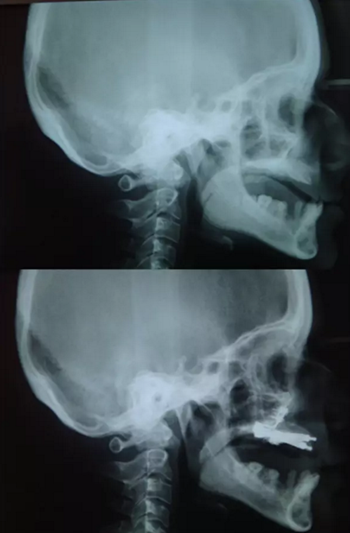

圖 3. 側(cè)位片(術(shù)前及牽張前)

該患者的治療目標(biāo)是恢復(fù)牙頜面的正常功能和美觀,包括頜骨的垂直關(guān)系及咬合關(guān)系。治療步驟分別是術(shù)前診斷,制備引導(dǎo)性義齒,外科手術(shù)(Le FortⅠ型截骨牽張成骨),種植體植入及最終的義齒修復(fù)。上頜牽張 10 天(每天 0.5 mm×2 次),二期拆除牽張器并行種植體植入,術(shù)后出現(xiàn)輕微的感覺(jué)異常及開(kāi)口困難,癥狀于 2 周后緩解。經(jīng)頭影測(cè)量可見(jiàn) A 點(diǎn)、ANS 點(diǎn)、上唇、鼻尖點(diǎn)分別前移 6 mm、 8 mm、5 mm、2 mm。最后行義齒修復(fù)上頜牙列缺失?;颊邔?duì)最終的美觀及功能恢復(fù)感到滿意。